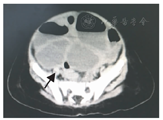

患儿,女,8月龄。因腹泻6 d并腹胀、呕吐1 d以不全性肠梗阻、水盐平衡紊乱收住院。入院前6 d患儿无明显诱因出现腹泻,腹泻物为黄色稀便,每天3~4次,在当地县医院诊断为"肠胃炎" ,予以输液治疗(具体药物不详)但症状无缓解。入院前1 d出现腹胀、呕吐,呕吐物为胃内容物,考虑"肠梗阻"而转来我院。病程中无喂养不当或不洁饮食史,无发热、血便等,食欲不振。体检:T 36.5 ℃,P 130次/min,R 27次/min,体重9 kg。精神萎靡,轻度脱水征,心肺检查未见异常;腹部膨隆,未见胃肠型及蠕动波,腹软,腹部触诊无哭闹,无腹肌紧张,未扪及包块,未引出明显反跳痛,腹中部叩诊呈鼓音;肠鸣音可闻及2次/min,弱而单调,未闻及气过水声;肛门指检未触及包块,退出指套仅粪染无血迹。辅助检查:血常规WBC 12.87×109/L、N 0.68、L 0.25,RBC 4.89×1012/L、Hb 122 g/L、HCT 0.37,PLT 747×109/L,hsCRP>5 mg/L,CRP 20.1 mg/L;电解质K+ 5 mmol/L,Na+ 131 mmol/L,Cl- 91 mmol/L,Mg2+ 1.17 mmol/L,Ca2+ 2.52 mmol/L;肝肾功能正常,大便隐血试验阴性;腹部X线平片、彩色超声及CT平扫均考虑肠梗阻(图1)。入院诊断:婴儿腹泻、轻度脱水、电解质紊乱、急性肠梗阻。

在术后回顾本例术前腹部CT表现,阑尾腔清晰可见(图1箭头所示),结合对入院后病情变化的观察和手术所见,本例应是在非侵袭性肠炎的基础上发生阑尾自身套叠,尽管发生阑尾套叠的机制不清楚,但发生炎症后阑尾壁水肿和管腔变狭小,先发生阑尾炎再套叠的可能性极小,在阑尾套叠的基础上继发阑尾急性化脓性感染符合阑尾炎发生的病因和病理基础。阑尾炎发生后,由于炎症渗出导致局部粘连诱发阑尾盲肠套叠即阑尾套入盲肠,随着套头向盲肠的深入而发生盲肠套叠,这一病理变化的发生才使腹部彩色超声能探及"同心圆征" ,但也使炎症的阑尾得以局部包裹,减少了炎症对腹腔和全身的影响,血液中仅WBC升高而其分类均无明显升高,腹水清亮且经培养无细菌生长。由于局部炎症的加重和对局部的刺激,导致回盲部水肿,加之同时存在盲肠套叠才影响回盲瓣的排空而引起不全性肠梗阻。因此,患儿前后两阶段病程中引起肠梗阻的原因是不同的,为初期的麻痹性和后期的机械性肠梗阻。